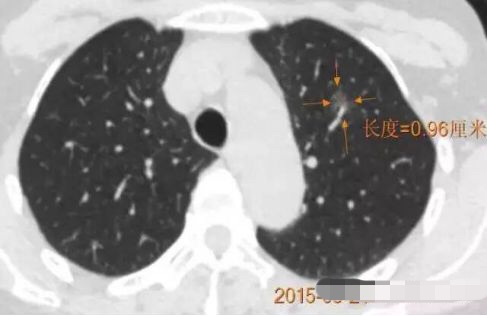

病例1 .

2014年 首次发现右肺上叶GGO,病灶直径8.3毫米, 2016年复查发现右肺上叶GGO,病灶直径12.4毫米。2年大约生长4毫米,平均1年生长2毫米。2016年手术病理结果:浸润性腺癌。

2014年 病灶8.3毫米